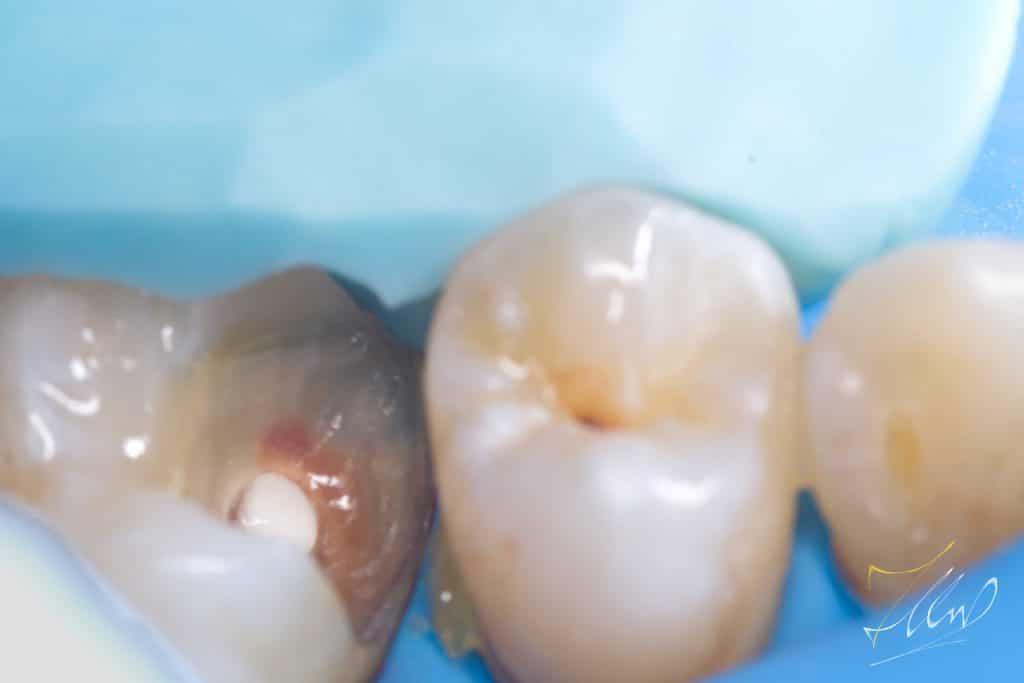

When caries are removed and the pulp is exposed, it can weaken the enamel. In such cases, it is advisable to create a silicone index after covering the exposed pulp with mineral trioxide aggregate (MTA). This should be followed by a precise cavity design and the removal of unsupported buccal cusp .